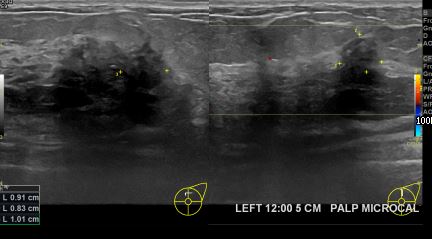

상기환자 외부검사상이상소견으로 내원해주신 60대여성분으로 좌측유방에 관찰된 미세석회부분조직검사하여 유방암진단되셨습니다.